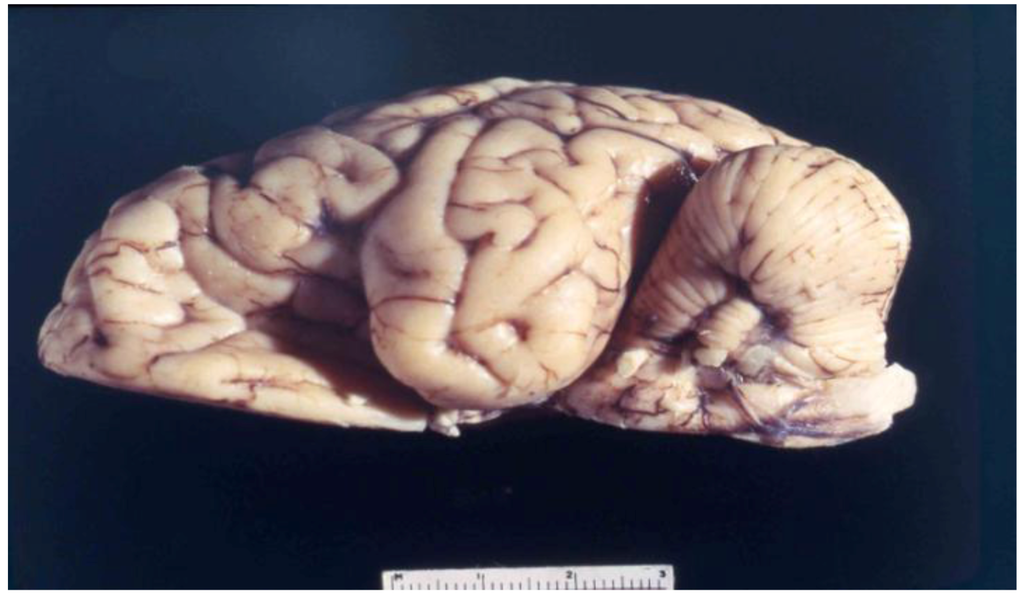

8. Neuropathology